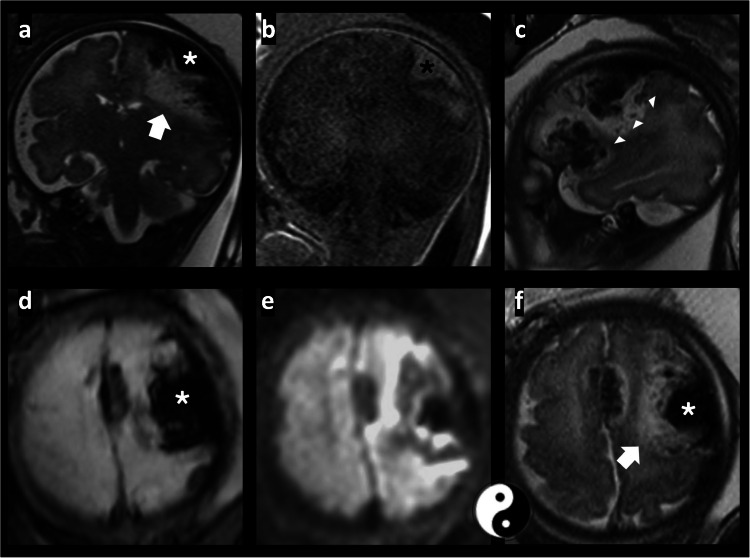

脑膜下出血是一种罕见的颅内出血,通常发生在新生儿身上。我们报告了一名28岁初产妇的首次产前诊断,胎儿磁共振成像(MRI)通过其特征皮质向内凹陷(“皮质屈曲”)和表观扩散系数图上的扩散受限来确定其脑膜下出血,后来通过尸检证实。本病例提示腹膜下出血的发病机制是胎儿的内在因素,而不是出生创伤或新生儿窒息,并强调了胎儿MRI在区分腹膜下出血和其他胎儿出血方面的关键作用,对产前咨询和围产期管理具有重要意义。

Subpial hemorrhage is a rare intracranial hemorrhage typically described in neonates. We report the first prenatal diagnosis of subpial hemorrhage in a 28-year-old primigravida, defined on fetal magnetic resonance imaging (MRI) by its hallmark cortical inward depression ("cortical buckling") and restricted diffusion on the apparent diffusion coefficient map, and later confirmed by autopsy. This case implicates intrinsic fetal factors-rather than birth trauma or neonatal asphyxia-in subpial hemorrhage pathogenesis and highlights the critical role of fetal MRI in distinguishing subpial hemorrhage from other fetal hemorrhages, with important implications for prenatal counseling and perinatal management.